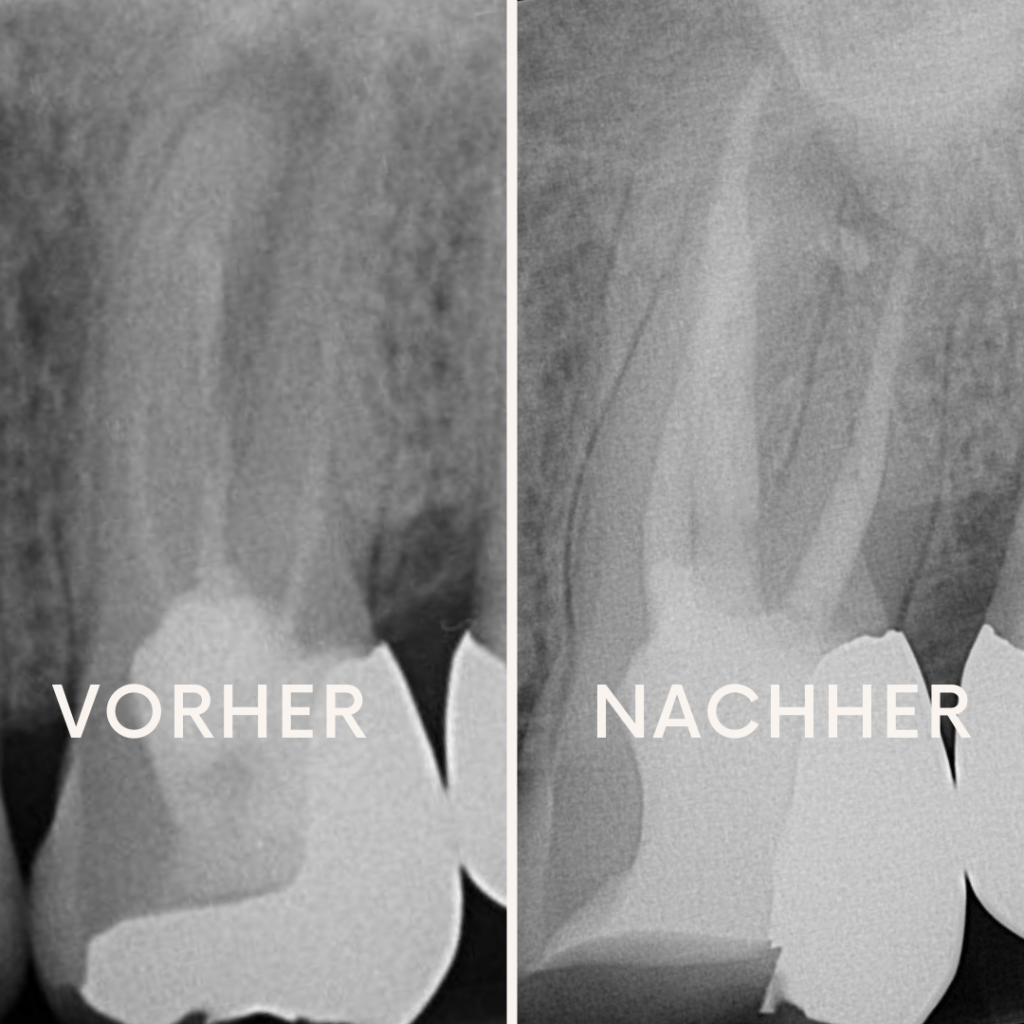

Fallbeispiel: Anwendung biokeramischer Wurzelfüllpaste